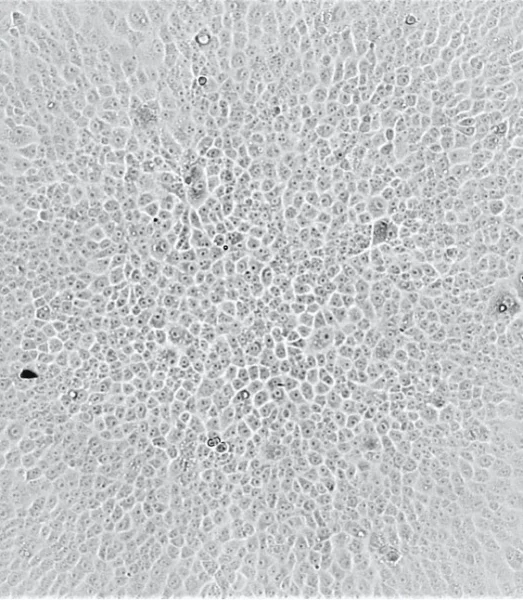

To test the ability of vaccine recipients' serum antibodies to neutralize the Omicron variant, the team used sera from two groups of vaccine recipients who have received two doses of BNT162b2 (BioNtech) or Coronavac.  Each group consists of 25 people.

Two Omicron variants present in Hong Kong were tested, one from South Africa and the other from Nigeria (with the additional R346K mutation). The ability of serum antibodies to neutralize the Alpha, Beta, and Delta strains was also tested as a control.

Only five out of 25 Biontech vaccine recipients had neutralizing ability against the Omicron variant virus, and the vaccine efficiency was significantly reduced to 20 - 24%. Compared to the original SARS-CoV-2 strain, the titer of neutralizing antibodies against the Omicron variant has decreased by 36 - 40 fold.

None of the serum of the 25 Coronavac vaccine recipients contain sufficient antibody to neutralize the Omicron variant at the limit of 1 in 10 dilution.